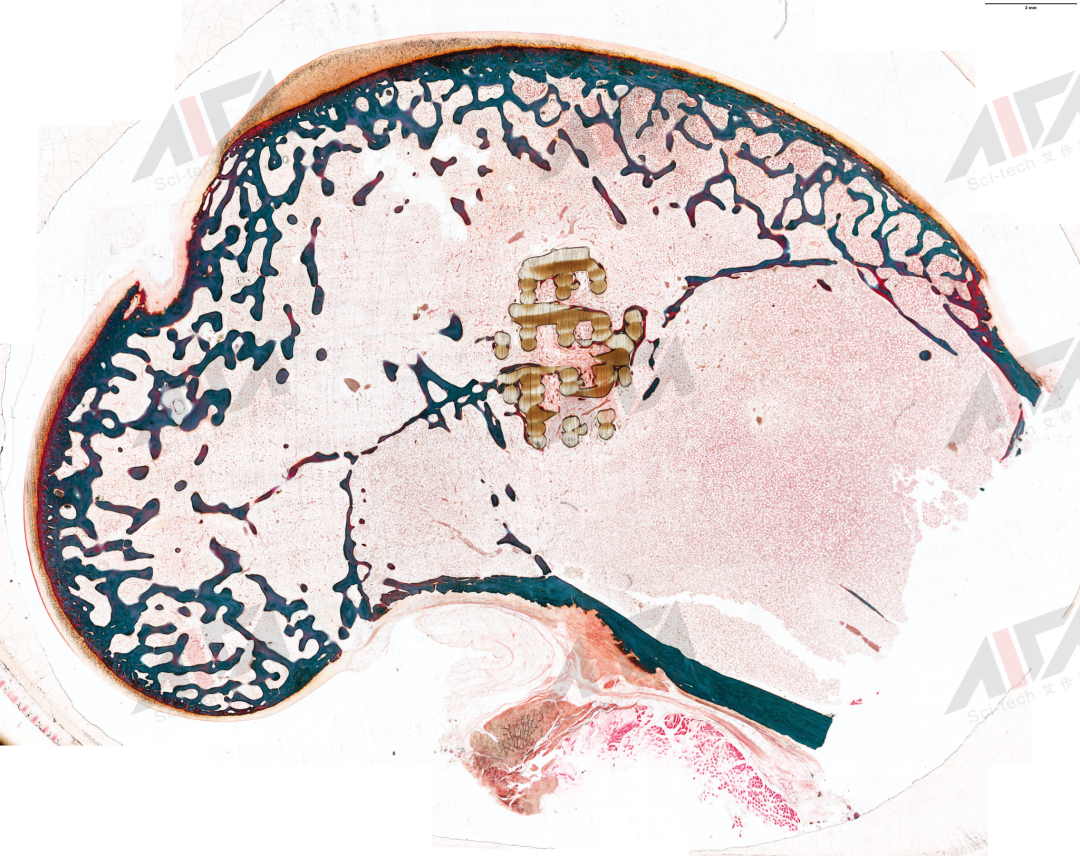

图片

硬组织切磨片 -甲-苯-胺蓝染色

硬组织切磨片 -HE染色